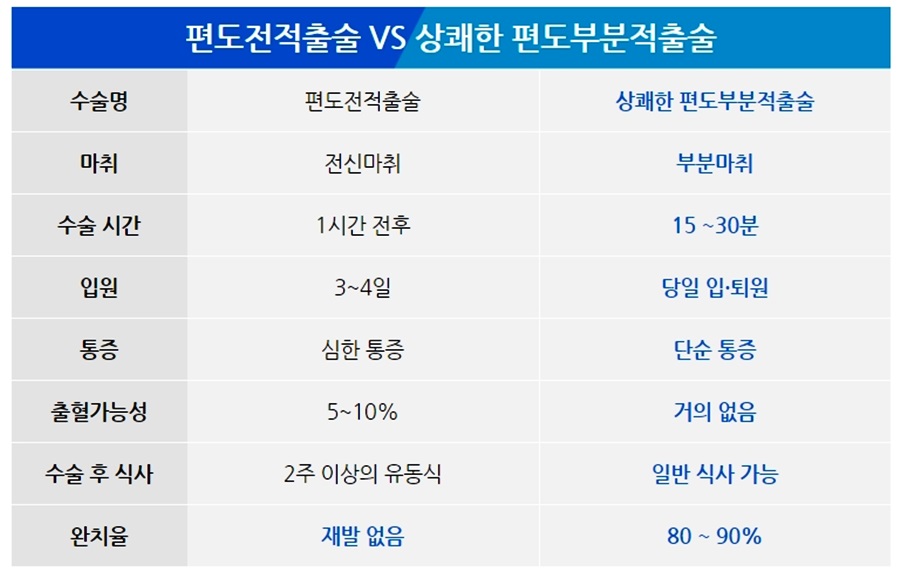

불쾌한 구취를 유발하고 일상생활에 불편을 주는 편도결석.오늘은 편도결석수술에 대한 정보를 알려드리고자 하는데, 이전에는 편도결석을 제거하기 위해 편도선 전체를 제거하는 방법을 사용했지만, 최근에는 정상적인 건강한 조직은 그대로 두고 문제가 되는 부분만 부분적으로 제거하는 치료를 시행하고 있습니다.

화성이비인후과 편도결석수술 부분절제술의 소요시간은 약 20분~30분이며 구토마취로 이루어집니다.일반적인 부담스러운 수술이 아니기 때문에 일상 생활의 복귀도 빠르고, 특별히 문제 없습니다.

편도결석은 우선 흡입기로 제거하지만 쉽게 재발할 수 있기 때문에 결석의 원인이 되는 편도선을 치료해야 합니다. 이 때 화성이비인후과는 고주파를 이용한 편도 결석 부분 절제 수술을 시행합니다.

편도선의 홈 깊이에 따라 약간의 차이는 있지만 편도선 전체를 제거하는 것보다 더 쉽게 치료와 회복을 할 수 있습니다.